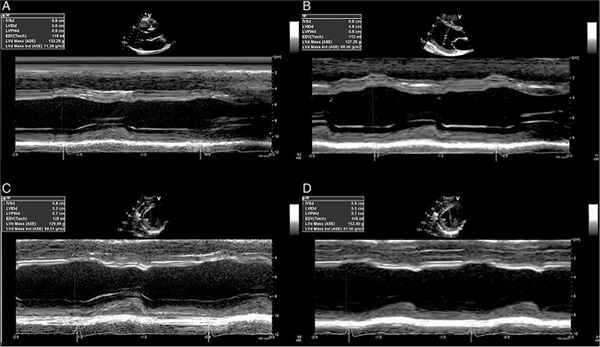

Определение ММЛЖ требует тщательного измерения толщины стенки и размеров камер. Линейные измерения внутреннего размера ЛЖ, его задней стенки (ЗС) и межжелудочковой перегородки (МЖП) выполняются по длинной оси из парастернального доступа приблизительно на уровне концов створок митрального клапана. Записи в М-режиме имеют прекрасное временное разрешение и могут быть выбраны из 2D-изображений. Однако даже при выполнении всех условий для получения качественного 2D-изображения не всегда удается выровнять курсор для получения изображения в М-режиме перпендикулярно длинной оси желудочка (рис. 1). Хотя программы для реконструкции изображений в анатомическом М-режиме из 2D разработаны (рис. 2), они не являются повсеместно доступными. Справочные нормальные значения линейных размеров ЛЖ можно найти в обновленных рекомендациях по измерению камер сердца. В качестве альтернативы размеры камер и толщину стенок можно получить из парастернального доступа по короткой оси, используя прямые 2D-измерения. Определение линейных размеров из 2D устраняет проблему угловых парастернальных изображений, которые приводят к переоценке размеров полости и стенки ЛЖ из М-режима (рис. 3).

Рис. 2. Реконструкция изображений в анатомическом М-режиме из 2D

Рис. 3. Использование 2D-изображений для определения систолических и диастолических размеров, располагающихся перпендикулярно длинной оси ЛЖ в месте соединения хорд и створок митрального клапана

На рисунке 1 изображено расположение курсора перпендикулярно длинной оси желудочка. Направление А перпендикулярно длинной оси ЛЖ, но не помещается в ультразвуковое окно (луч должен пройти через грудину). Направление В располагается под углом к перпендикуляру оси ЛЖ и является неприемлемым. Если нет другого окна, могут потребоваться измерения в анатомическом М-режиме или прямые измерения в 2D.

Переоценка размеров ЛЖ (рис. 2) может иметь место из-за отклонения изображения под углом к требуемой оси (А). Когда ультразвуковое окно не может быть сдвинуто, альтернативой может послужить получение точных данных путем реконструкции М-режима из изображений в 2D – так называемый анатомический М-режим (В). На этом примере небольшое отличие (1 мм) в конечно-диастолическом размере (КДР) ЛЖ обусловливает отличие ММЛЖ в 5 г. Угловые изображения могут приводить не только к более длинным срезам, но и к переоценке размеров из-за невозможности пройти лучом через ось ЛЖ (С). Использование анатомического режима может устранить эту проблему (D).

При использовании 2D-изображений толщина стенок и линейные размеры должны быть измерены на уровне минимального размера ЛЖ, на уровне концов створок митрального клапана. Верхняя граница нормы для КДР меньше, чем при измерениях в М-режиме. КДР, МЖП в диастолу (МЖПд) и ЗС в диастолу (ЗСд) измеряются в конце диастолы в 2D или М-режиме предпочтительно в нескольких кардиоциклах.